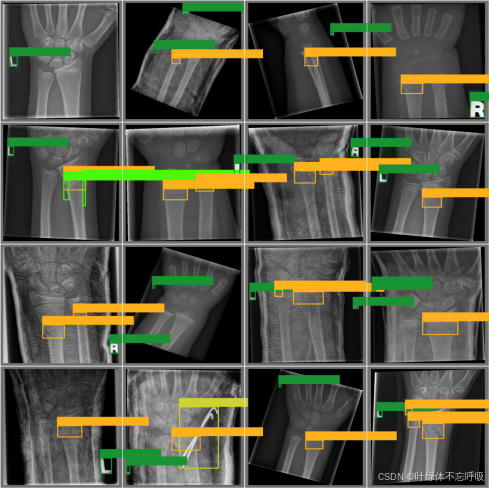

数据集收集是构建任何机器学习或深度学习模型的第一步,对于该目标检测系统,骨折等骨损伤的X光片数据集来源GRAZPEDWRI-DX数据集,对收集到的图像进行筛选,去除质量低下、不清晰或者与目标类别无关的图像。并对收集到的原始图像数据中不完整的图片进行标注。数据标注是将图像中的每个目标用边界框标出,并为其分配相应的类别标签,这一步骤对于模型学习识别和定位目标至关重要,本设计选择LabelImg工具进行标注,如图3.2所示。

GRAZPEDWRI-DX 数据集包含 2008 年至 2018 年间在格拉茨大学医院儿科外科治疗的 6,091 名患者的带注释的儿科创伤腕部 X 光片,共有 10,643 项研究(20,327 幅图像)可用,覆盖前后和横向投影。该数据集带有 74,459 个图像标签和 67,771 个标记对象。通过LabelImg软件对所有收集的图片进行标注,先标注为XML格式,再通过Python脚本转换为YOLO格式,并将其进行划分。处理完成的数据集一共有16878张图片用于训练,3449张图片用于验证。检测的类别包括boneanomaly(骨异常)、bonelesion(骨损伤)、foreignbody(异物)、fracture(骨折)、metal(金属)、periostealreaction(骨膜反应)、pronatorsign(前臂神经损伤)、softtissue(软组织损伤)和text(文本标签)共9类,其中有216个boneanomaly、33个bonelesion、6个foreignbody、15064个fracture、647个metal、2890个periostealreaction、471个pronatorsign、377个softtissue和19707个text标注目标对象。将处理过的数据集输入YOLO算法进行模型训练,数据集中的目标数量如图3.3左上角所示,其显示了各个检测类别包含的样本数量;目标框的尺寸和数量如图3.3右上角所示,其展示了训练集中边界框的大小分布以及相应数量;目标框中心点相对于整幅图的位置坐标如图3.3左下角所示,其描述了边界框中心点在图像中的位置分布情况;数据集中目标相对于整幅图的高宽比例如图3.3右下角所示,其反映了训练集中目标高宽比例的分布状况。